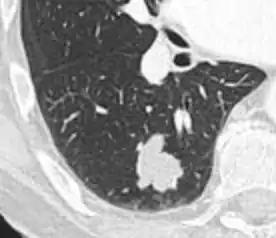

Spiculated lung nodule.[9]

A "notch sign".[9]